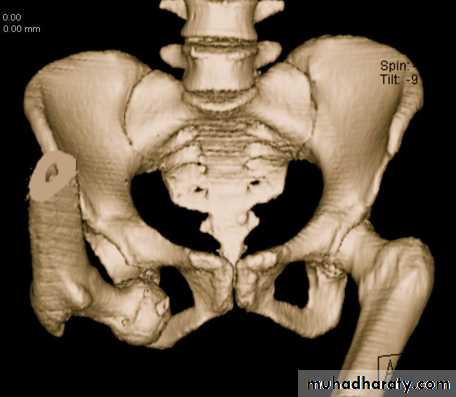

Central dislocation of the hip

fall on the side or blow over the greater trochanter may force the femoral head medially through the floor of the acetabulum .Although it is called central dislocation of the hip , it is really a fracture of the floor of the acetabulum